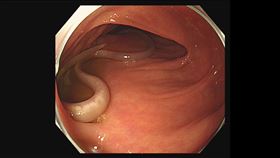

他暴瘦卻肚子脹!醫一看盲腸有「鵝卵石」

瘦到折磨人!肝膽腸胃科醫師葉秉威透露,日前遇到一名瘦...